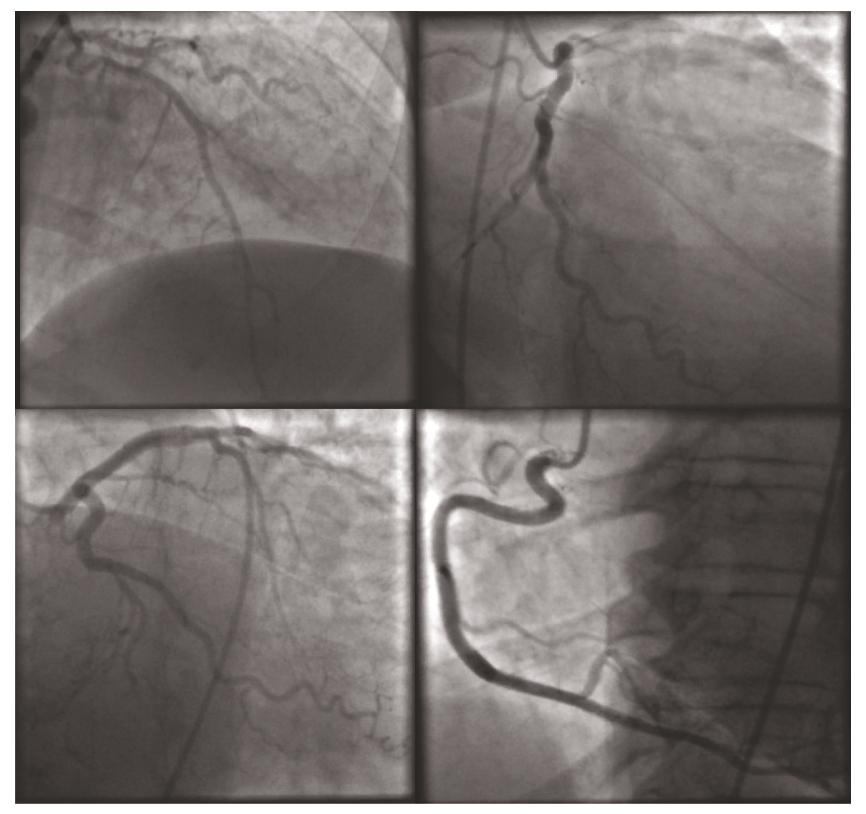

考虑到患者高龄,具有多个冠心病危险因素,有胸痛症状,心电图伴有T波的倒置,心肌酶升高,并且伴有动态变化,诊断为非ST段抬高型心肌梗死,给予负荷剂量的阿司匹林和波立维,并给予普通肝素泵入,而后进行了冠脉造影,预料之外但在情理之中,患者的冠脉再一次证实,患者冠脉并无明显狭窄(图3)。

图3:冠脉造影未见明显冠脉狭窄